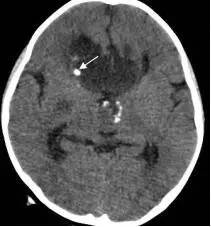

鉴于肿瘤体积超大,而且患儿间断出现意识障碍,直接作手术完全切除肿瘤的难度很大,为降低手术风险,所以我们采用先穿刺肿瘤囊减少肿瘤体积,降低颅压,二期手术争取完全切除肿瘤的策略。行肿瘤囊肿穿刺后,引流出约100多毫升囊液,肿瘤体积显著变小,见图3、图4。

图4.肿瘤囊穿刺手术后肿瘤体积减小

白色箭头示引流管